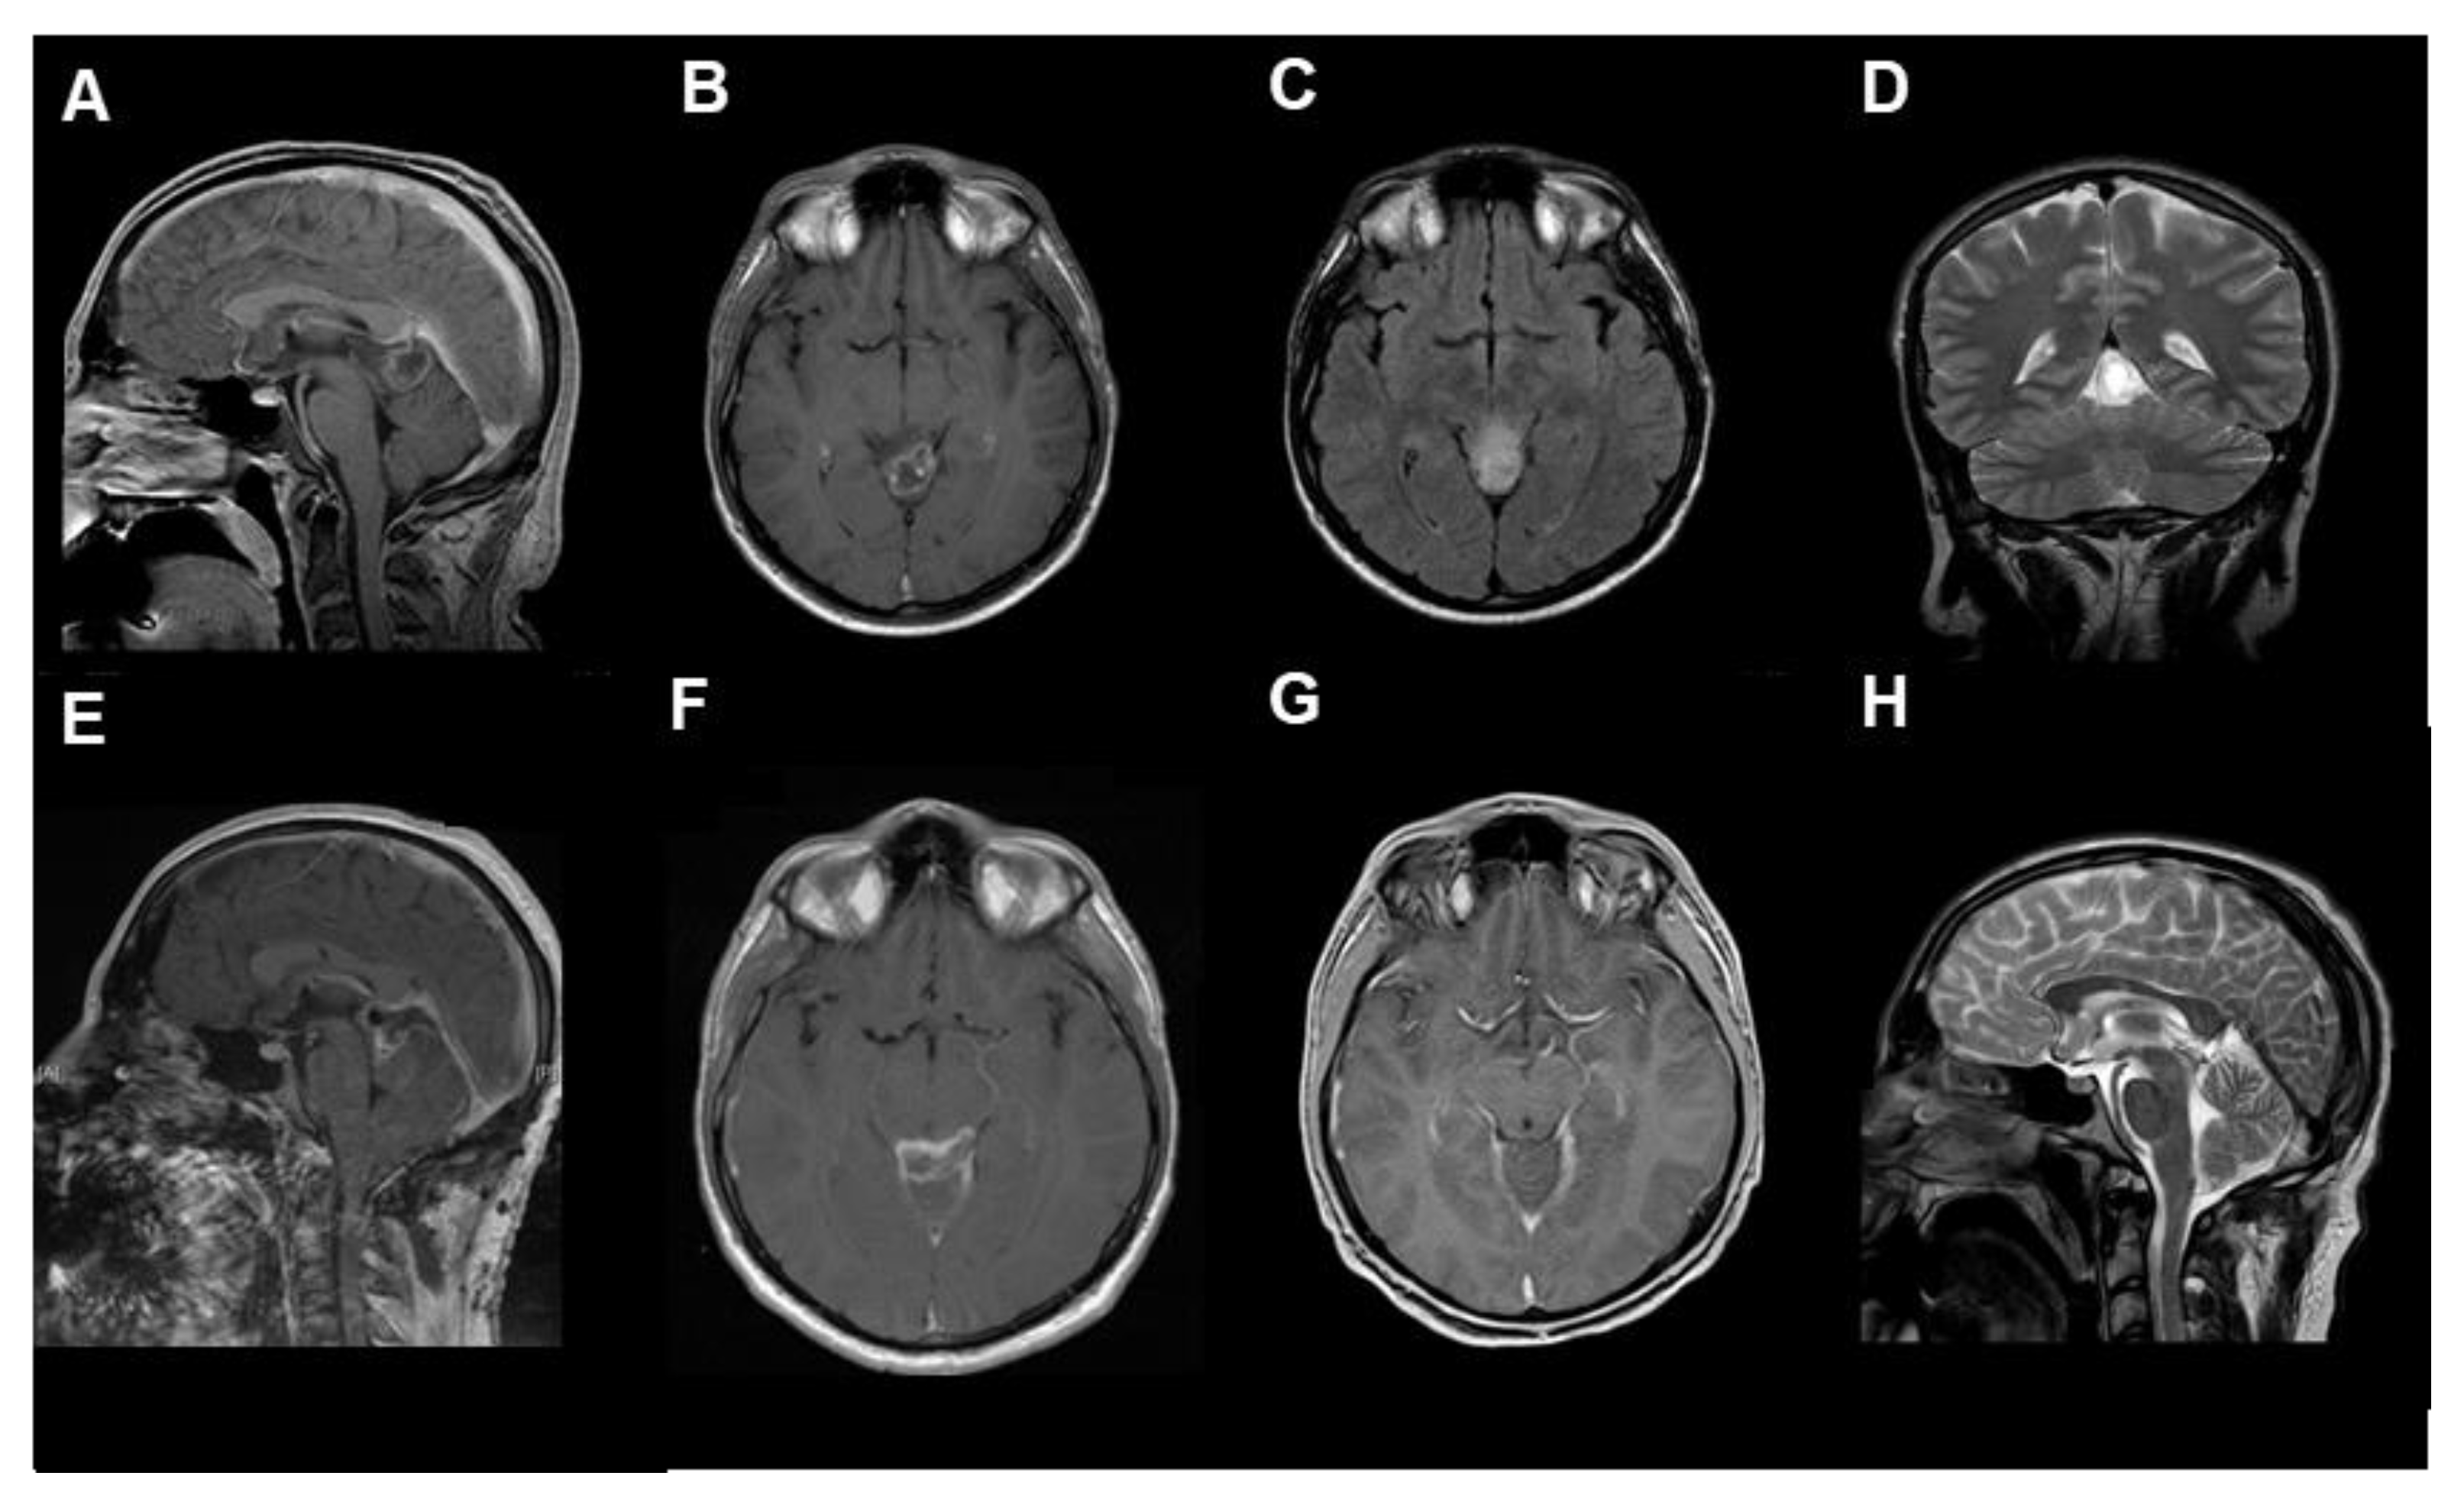

Figure 2.

The radiological findings of RGNT in the pineal region ((A–D) preoperative, (A,B): T1-weighted with contrast medium, (C): T2 flair-weighted, (D): T2, (E,F): postoperative, T1-weighted with contrast medium, (G,H): 3-months follow-up, (G): T1-weighted with contrast medium, (H): T2-weighted), from the first case, a 23-year-old male patient who presented with chronic headache.

- Case 1:

A 23-year-old male patient presented with chronic headaches for several months. An MRI scan diagnosed a cystic, ring-enhancing lesion (27 × 24 × 23 mm) adjacent to the pineal gland. GTR of the tumor was achieved. After an uneventful postoperative course, the patient could be discharged home without any neurological deficit 10 days after surgery. At 15 months follow-up, there were no new neurological deficits. Due to restricted psychological and mental capacity, the patient was unable to work. Follow-up MRI showed no residual or recurrent tumor.